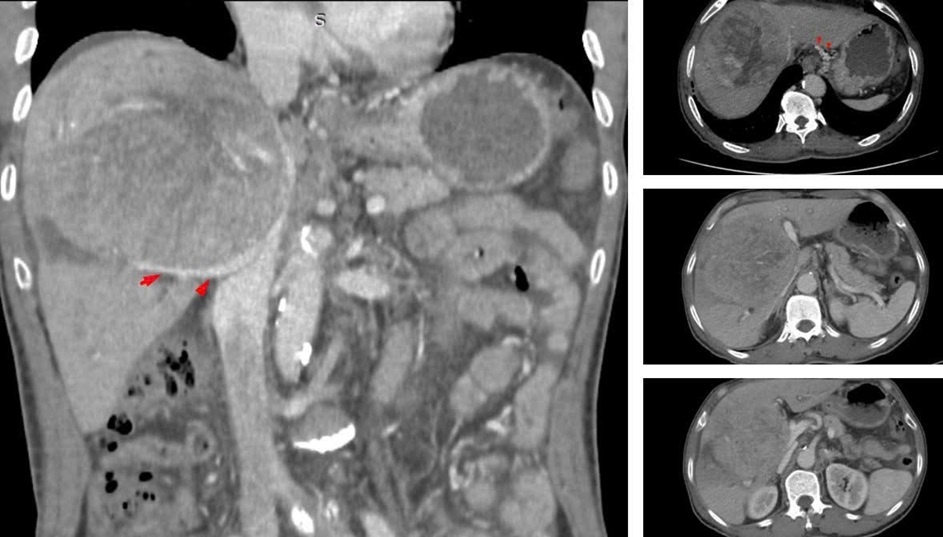

Khi kiểm tra, kết quả khối u gan đã đạt kích thước khổng lồ 10-12 cm. Tại một số cơ sở y tế, ông từng nhận được tiên lượng thời gian sống còn lại có thể không quá 9 tháng.

Theo bác sĩ chuyên khoa II Nguyễn Trường Giang, Phó Giám đốc Trung tâm Phẫu thuật Gan mật - Tiêu hóa, Bệnh viện Bệnh Nhiệt đới Trung ương, ngay khi tiếp nhận, đây đã là một ca bệnh rất nặng. Khối u khổng lồ chiếm gần hết nhu mô gan, chèn ép rốn gan và tĩnh mạch, gây ra tình trạng cổ chướng nhẹ và phù hai chân.

Khi kiểm tra, kết quả khối u gan đã đạt kích thước khổng lồ 10-12 cm.